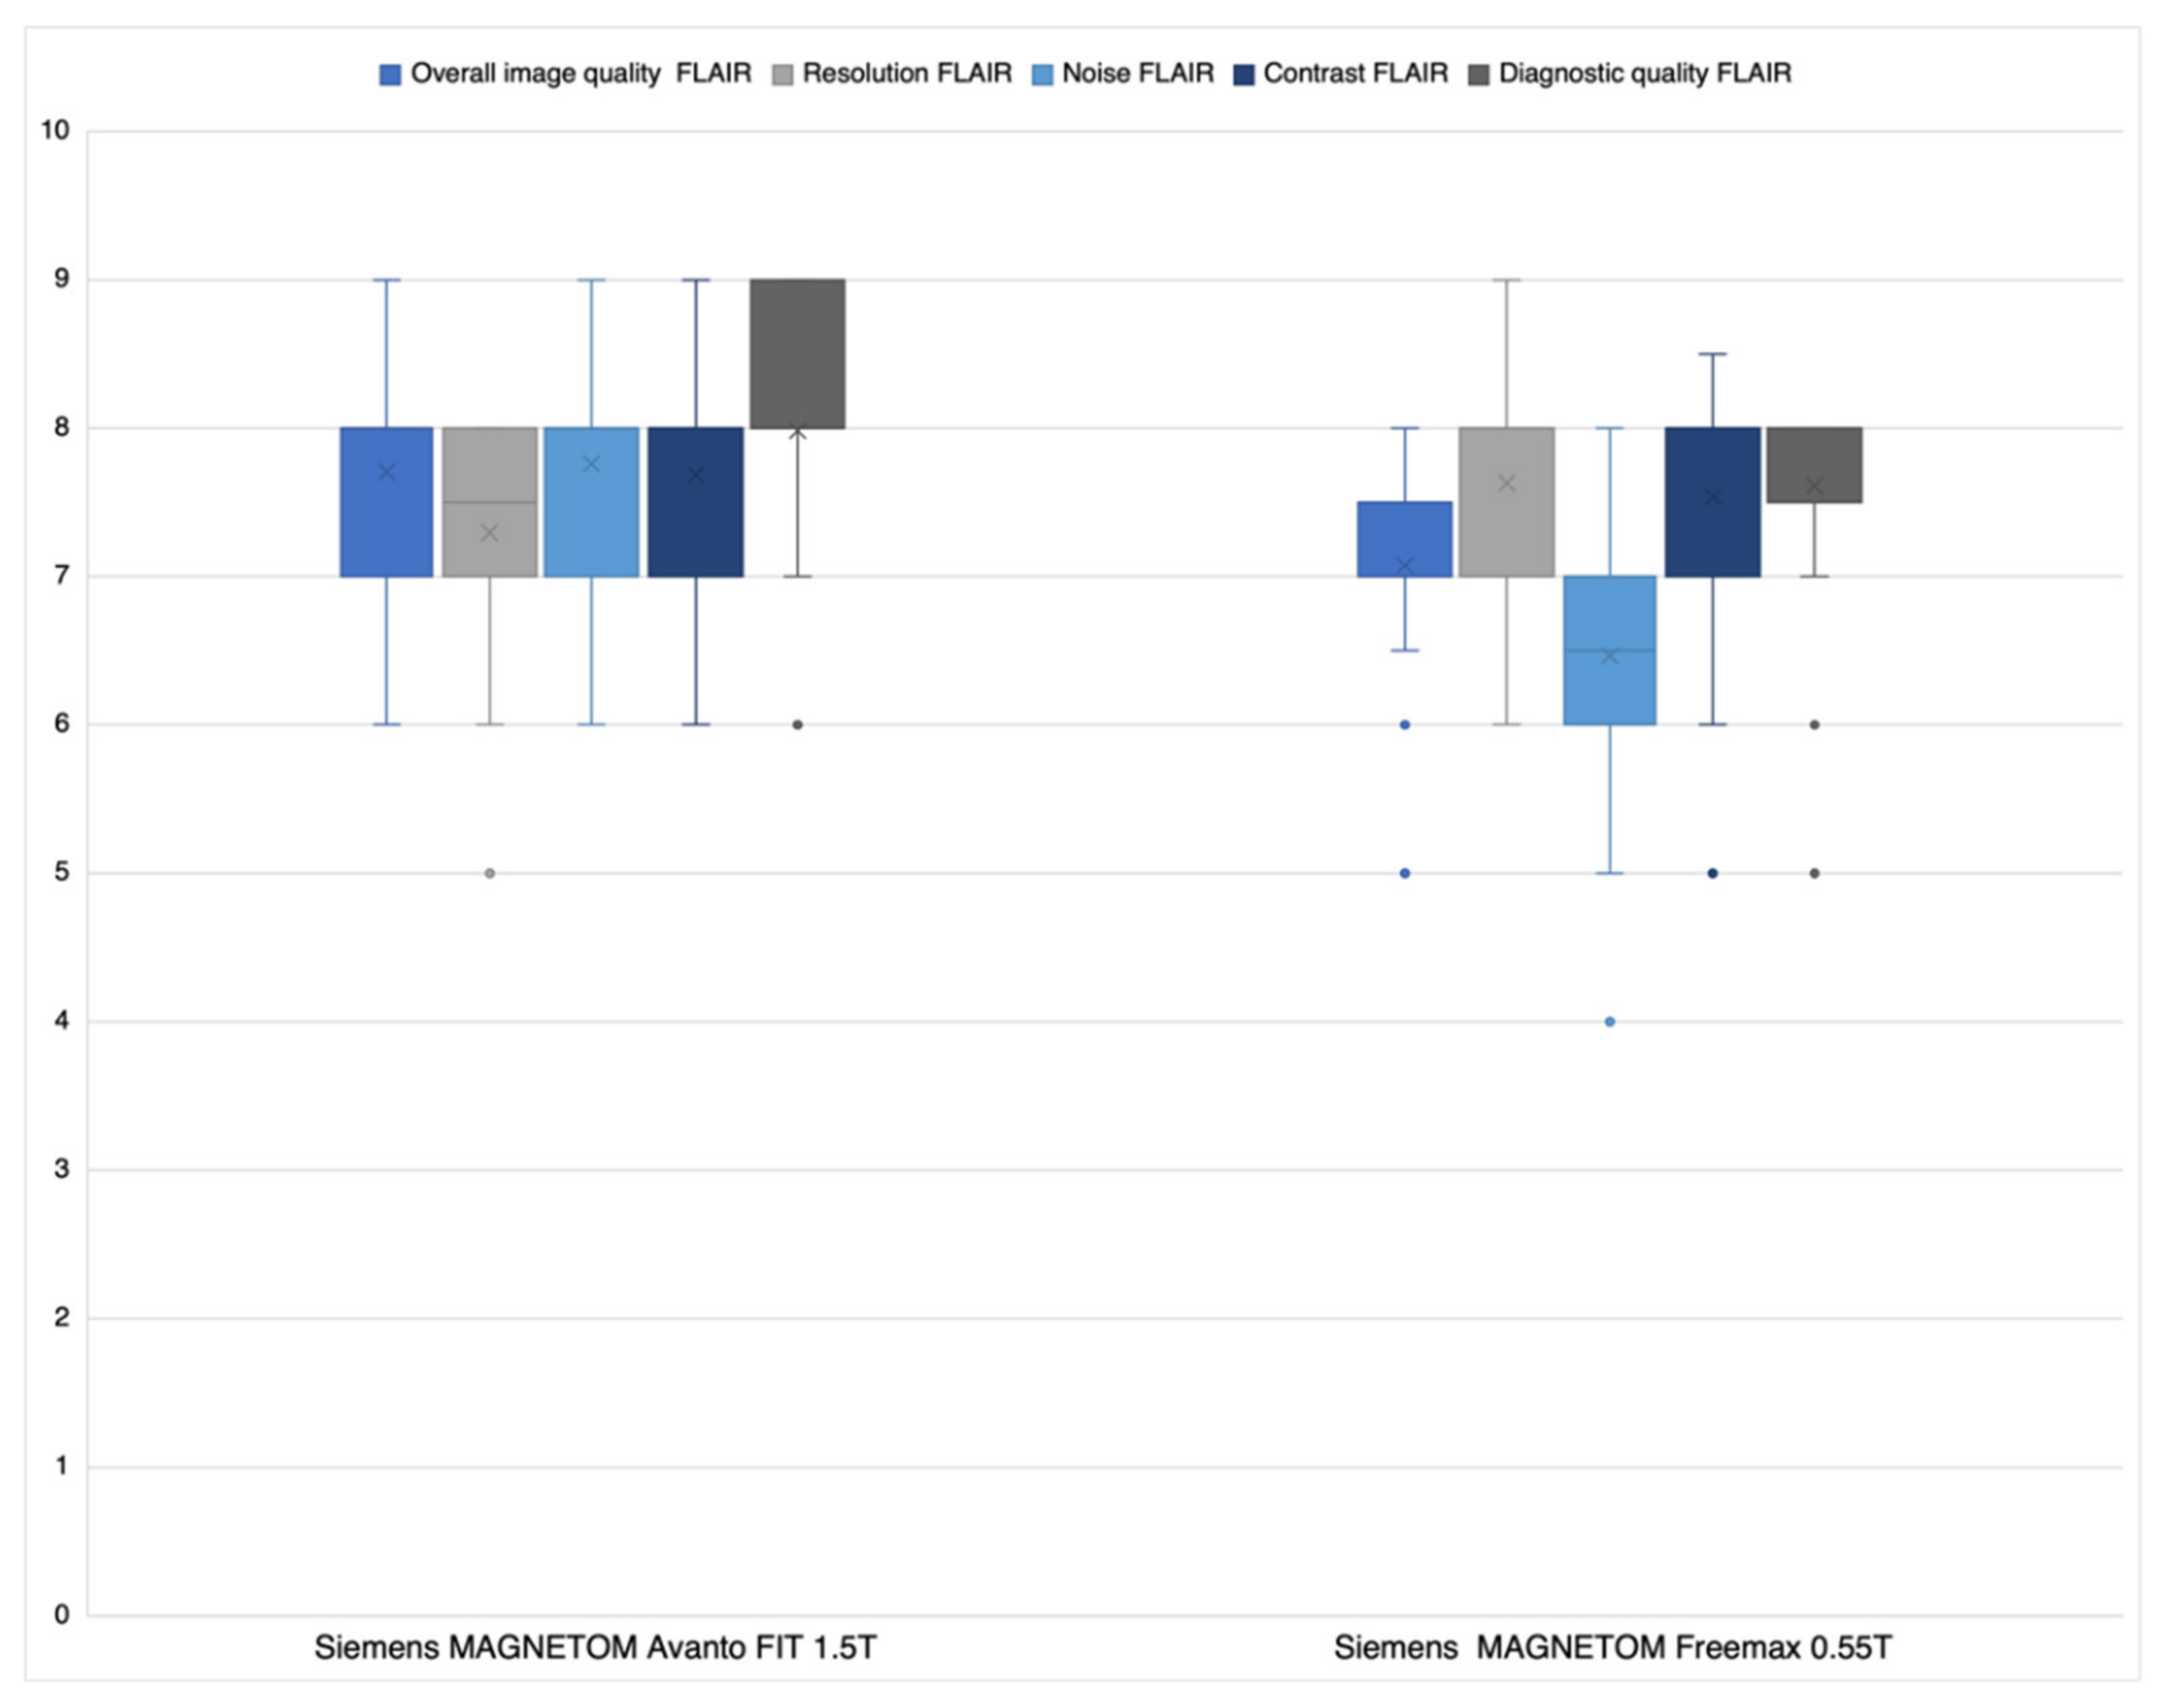

3.1. Likert Rating

3.1.2. FLAIR Datasets

4.1. Likert Rating